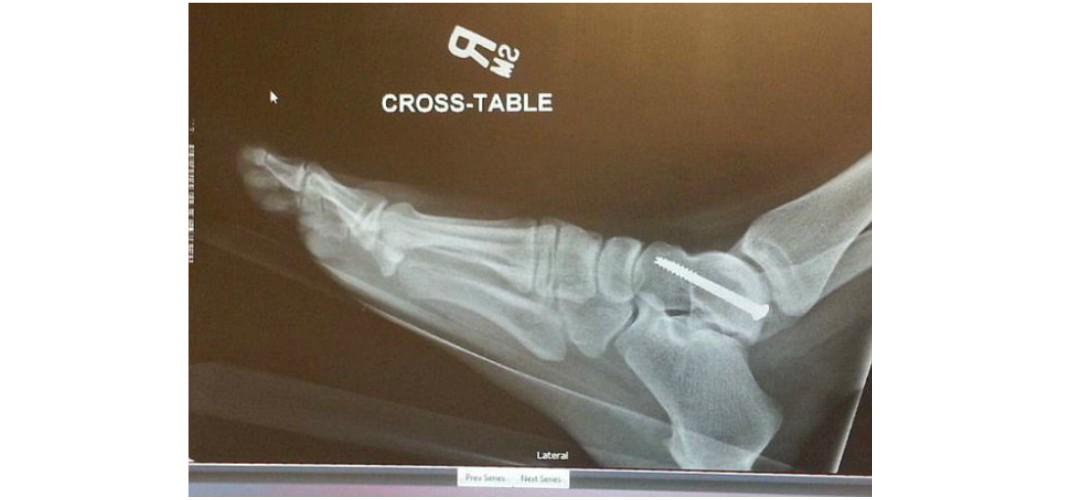

Η Οντρα Τέιτουμ, είναι πλέον άτομο με αναπηρία η οποία προκλήθηκε μετά από τροχαίο ατύχημα που την άφησε με δύο βίδες στον αστράγαλο, δύο στο ισχίο της, δύο στο γόνατό της και ανίκανη να σταθεί πάνω από τέσσερις ώρες.

Όταν συνέβη το ατύχημα, ο αερόσακος κυριολεκτικά εκτόξευσε το πόδι στο πρόσωπο της, σπάζοντας τον αστράγαλο, τη μύτη και το μηριαίο οστούν σε τέσσερις θέσεις.

«Ο αερόσακος άνοιξε και πέταξε το πόδι στο πρόσωπό μου, με αποτέλεσμα να σπάσω τη μύτη μου», είπε. «Έβλεπα το κάτω μέρος του ποδιού μου να κοιτάζει προς τα πάνω. Βασικά ολόκληρη η δεξιά πλευρά μου ήταν σπασμένη, και αυτό συνέβη λόγω της άγνοιας μου. Δεν είμαι ο Σούπερμαν. Δεν θα μπορούσα να πάρω το πόδι μου εγκαίρως».

Γράφει λοιπόν σε ποστ στο Facebook: «Πριν από δύο χρόνια ένας άντρας με κλεμμένο αυτοκίνητο μπήκε μπροστά μας. Ήμουν συνεπιβάτης. Τον χτυπήσαμε με περίπου 70 χλμ / ώρα. Το πόδι μου ήταν στο ταμπλό. Ο αερόσακος άνοιξε ... το πόδι μου έσπασε τη μύτη μου. Η μύτη έσπασε τον αστράγαλο. Το μηριαίο οστό έσπασε σε 4 κομμάτια. Και ο βραχίονάς μου έσπασε προσπαθώντας να σταματήσω την πρόσκρουση. Έχω τόσες βίδες και λάμες και είμαι χάλια μέχρι σήμερα!